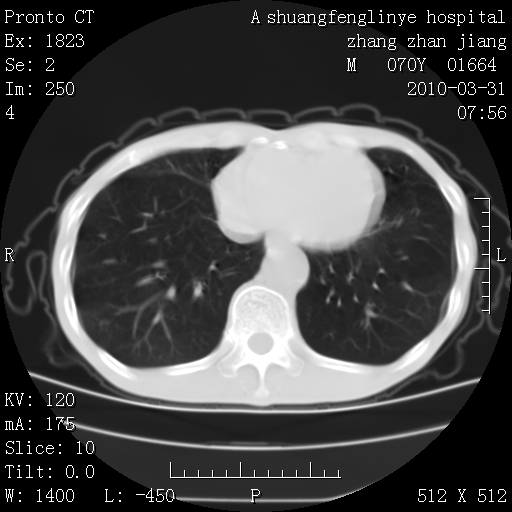

双上肺继发型tb并左上空洞形成,主动脉冠脉钙化。

1)两肺上叶继发性肺结核并左肺上叶空洞形成。2)冠状动脉及主动脉钙化。